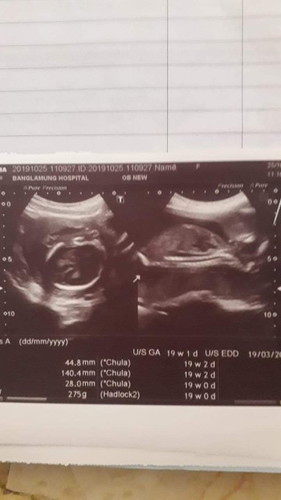

แม่ๆคนไหนท้อง 19วิด กี้เดือนค่ะ หมอนัดอัลตร้าซาว์เมื่อวานนร้หมอไม่ได้บอกไรเรย ไห้ดู เราดูไม่ออกเรยค่ะ ภาพอัลตร้าซาว์เมื่อวานนี้ เเต่หมอไม่พูดอะไรเรย ปกติใช่ไหมค่ะ